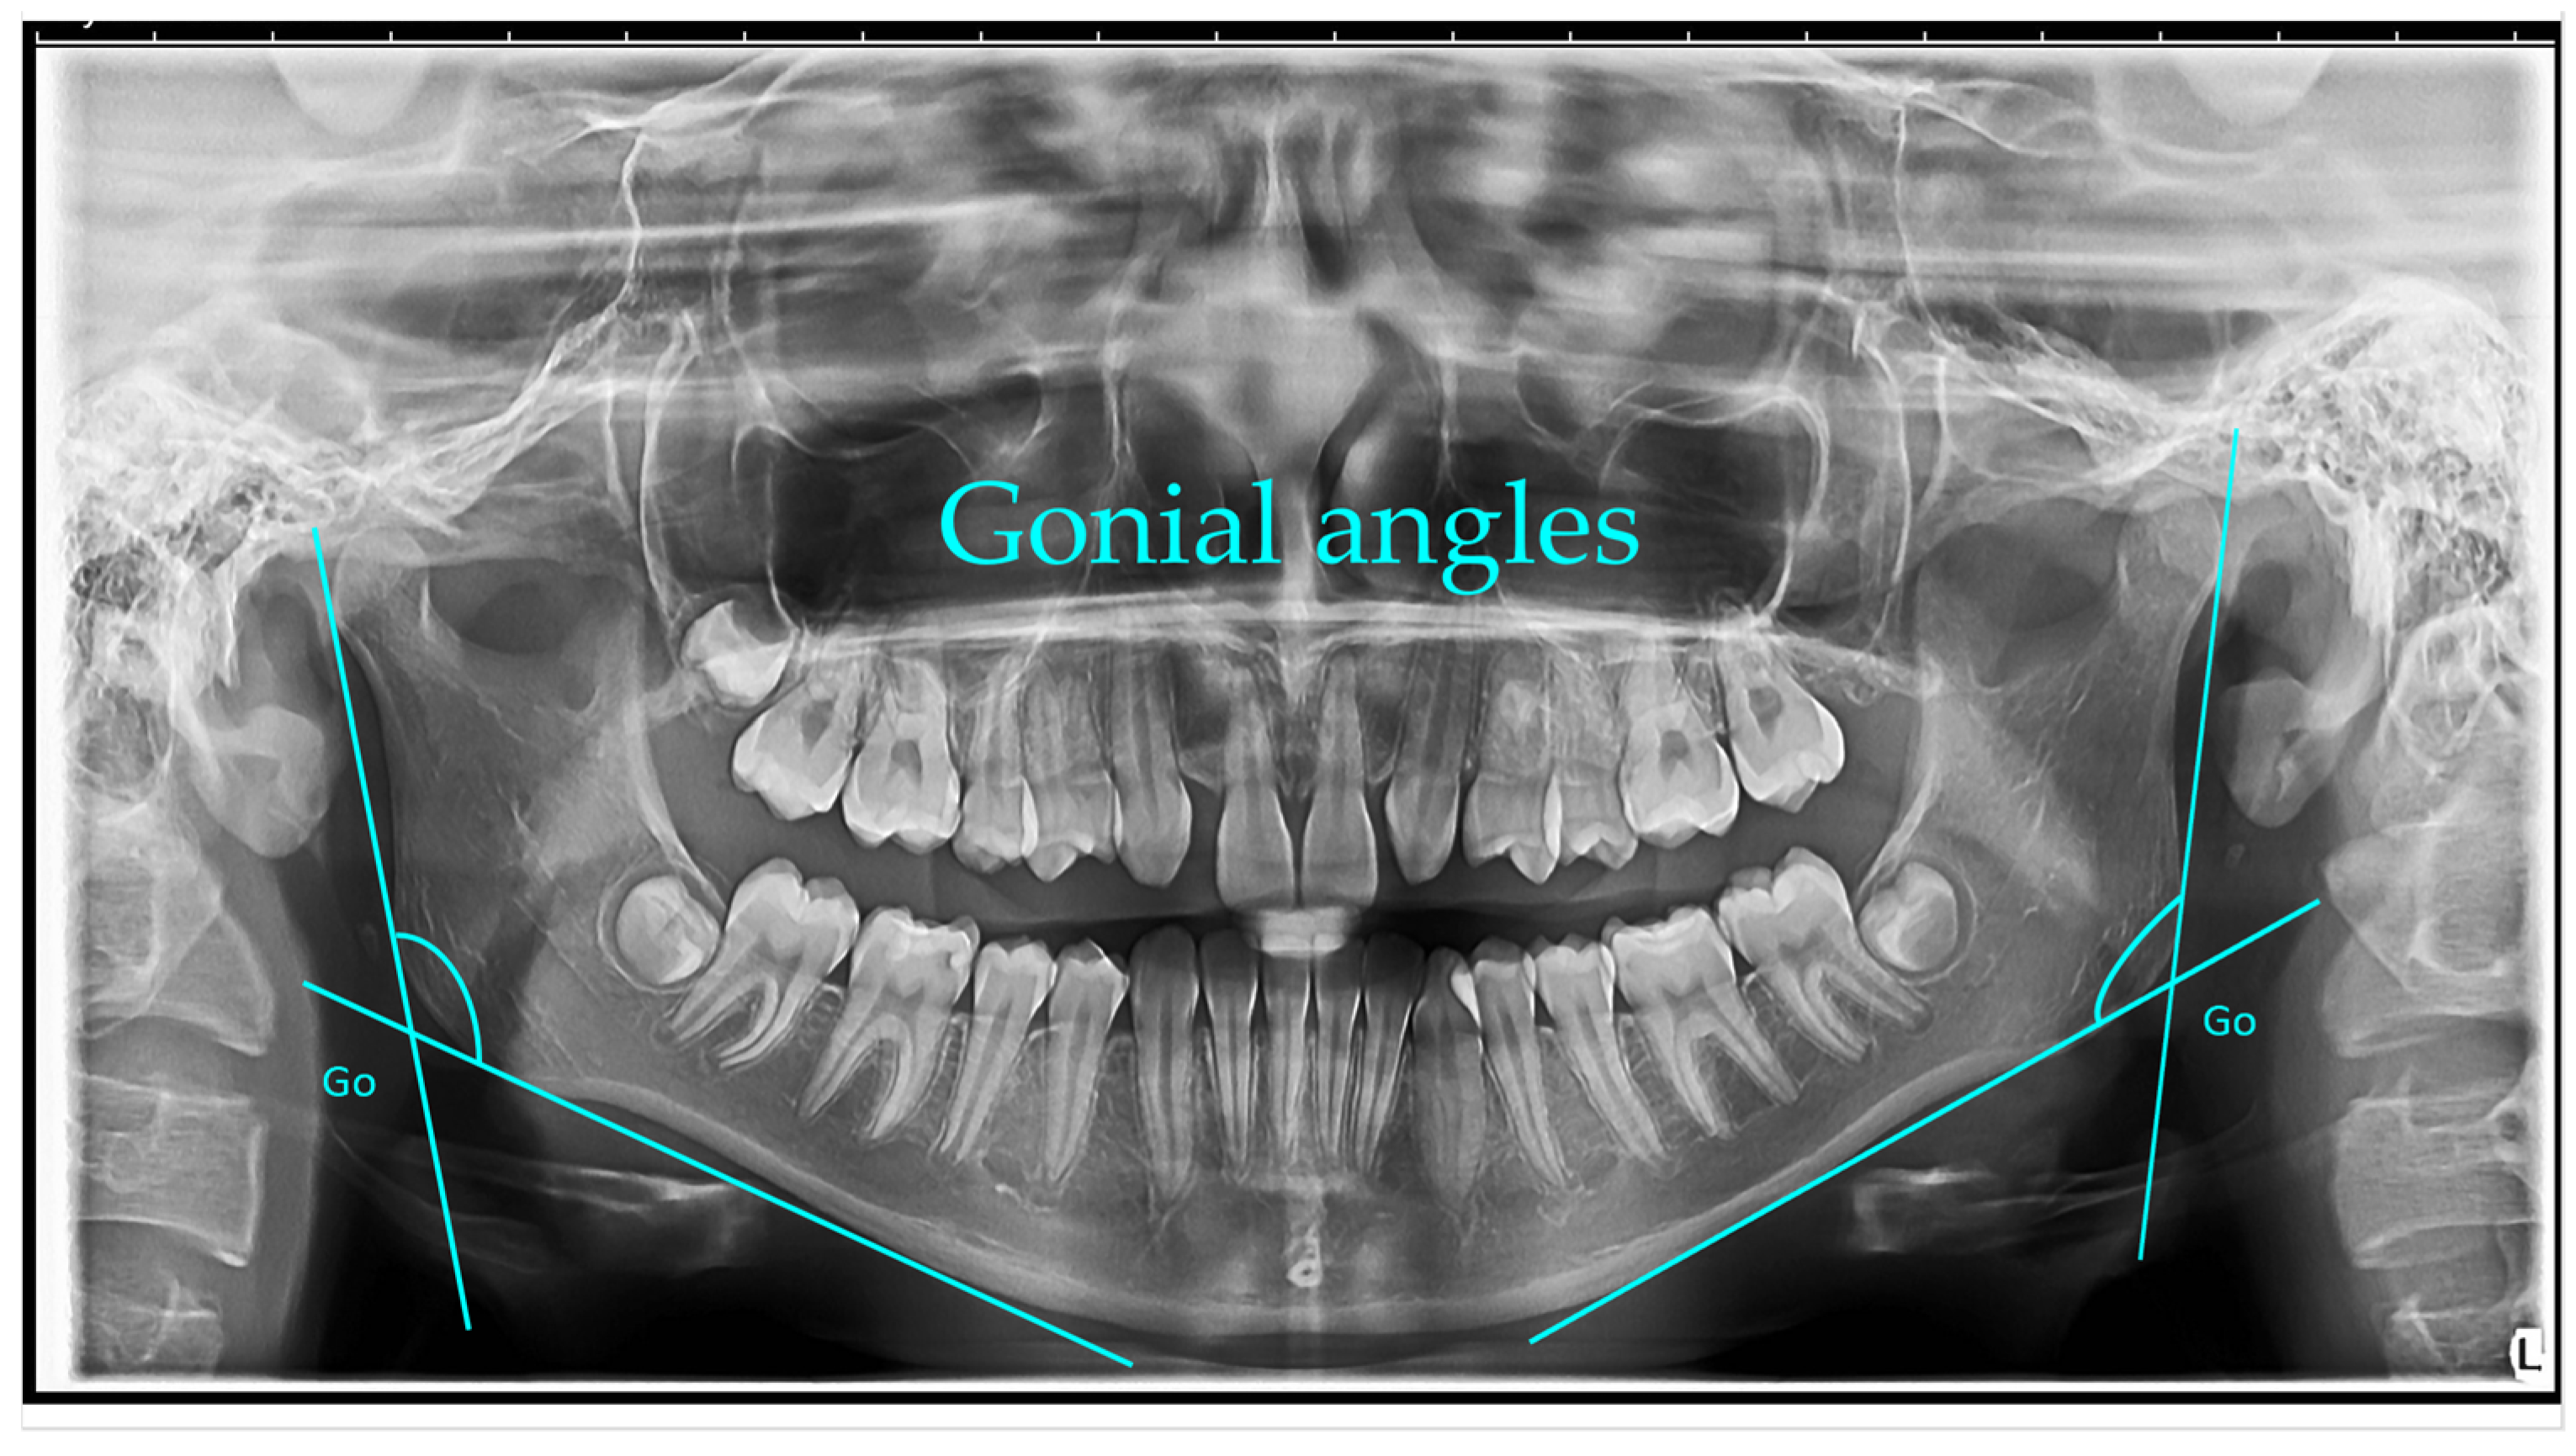

2 D OPG

A panoramic radiograph is a panoramic scanning dental X-ray of the upper and lower jaw. It shows a two-dimensional view of a half-circle from ear to ear.